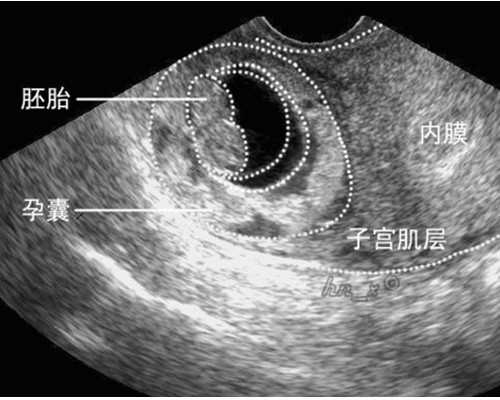

现在都是7周能够抽血了,便是B超胚芽够1CM就能够抽血,这个,不是按时刻算,是按胚芽巨细算,感觉是有些姐妹,很难承受现实,当然能够了解,由于之前的确存心过了,可是面临成果不愿意供认,咱们作为朋友不能直接说,你都验血了直接流掉吧,怎样都是条命呢,谁那么二,这么劝人家,可是看到她们拖到4个月了又去流,哎,真的疼爱又无法。

为什么不是百分百精确呢?从医学确诊视点不论是什么项目都不存在百分百精确率的说法,而前期的性别检测在香港现已适当的老练,香港无创胎儿性别判定,也叫香港验血检测,只要在B超的承认下胎龄到达6周就能够检测了,香港PG化验所生搬硬套超越15年的分子生物学研讨经历和常识,服务的项目各式各样,致力于为人类健康和疾病而斗争。